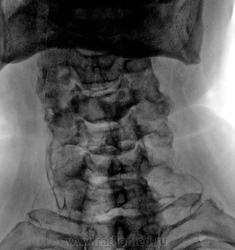

Интересное совпадение, сегодня вот такая шея попалась,к сожалению на боковой не вошло

Видимо ошибся, думал что на моем прямом снимке, связка это-(указано красной стрелкой), а это видимо просто обызвествление хряща

обызвествление выйной связки +Форестье.

Почему-то часто такое вместе встречается

Валентин Львович, ну а теперь оно?(обызвествление выйной связки)  Сегодня привели с травматологии.

ну а теперь оно?(обызвествление выйной связки)

Интересный снимок.